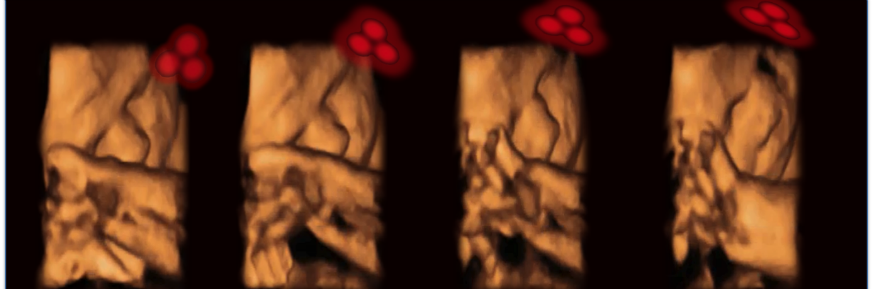

The team used a light source to project a pattern of three dots in the shape of eyes and a mouth through the uterine wall and measured the way the fetus responded using ultrasound.

The findings show that fetuses of 34 weeks gestation will turn their head to track the face-like pattern.

But there was no such movement when the team projected three inverted dots in the shape of a triangle, demonstrating that it was not the pattern itself which the fetus preferred.